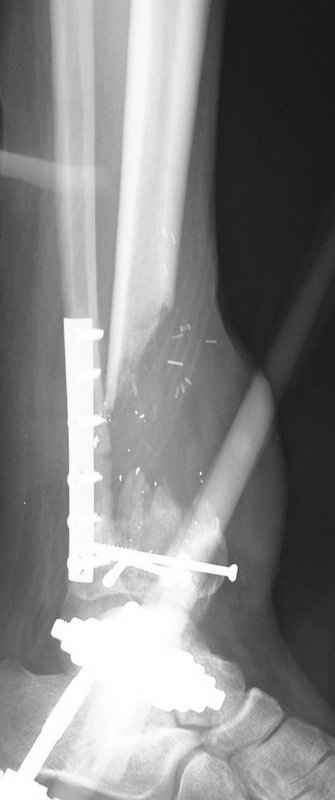

Реализовал описанную выше методику, и в итоге вот что получилось. Высылаю лишь прямые проекции,

Очень пригодились карбоновые кольца (Джолдас -огромное спасибо, я твой должник!!!), поскольку остеопороз дистального отломка был просто невероятный. На цифровом рентгене с трудом угадывались контуры.

Рентген в процессе перемещения - внизу карбоновые кольца, тракция фрагмента спицами с упором.

внешний вид в аппарате - не завершающем этапе, сначала стопа тоже была фиксирована в аппарате.

Сейчас аппарат сняли, но случай ещё не завершенный.

Признаюсь честно, не совсем уверен в прочности консолидации на стыке косточек. Кроме того, укорочение в районе 6 см. Сейчас реабилитация - ходит опираясь на ногу с одним костылем.